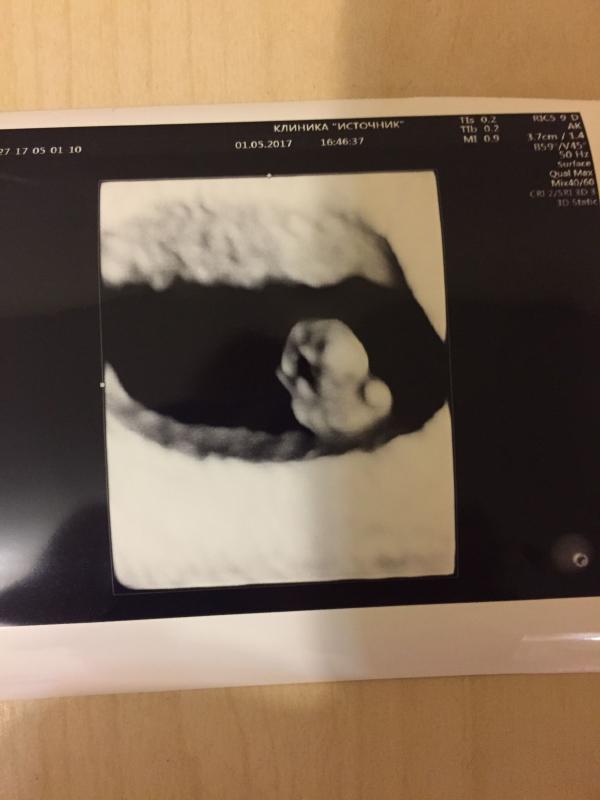

Дождалась!!! 💥💥💥Десять дней тянулись очень долго, мысли не давали покоя, как бы ни старалась гнать их прочь. Мучительно долгие и психологически сложные десять дней! Прошли все симптомы и казалось уже ничего не чувствую, готовилась к самому страшному. Но УРРРААА, все в порядке! Вот и моя "уточка", сердечко бьется, развитие в норме. Теперь будем бояться дальше🤣🤣🤣!